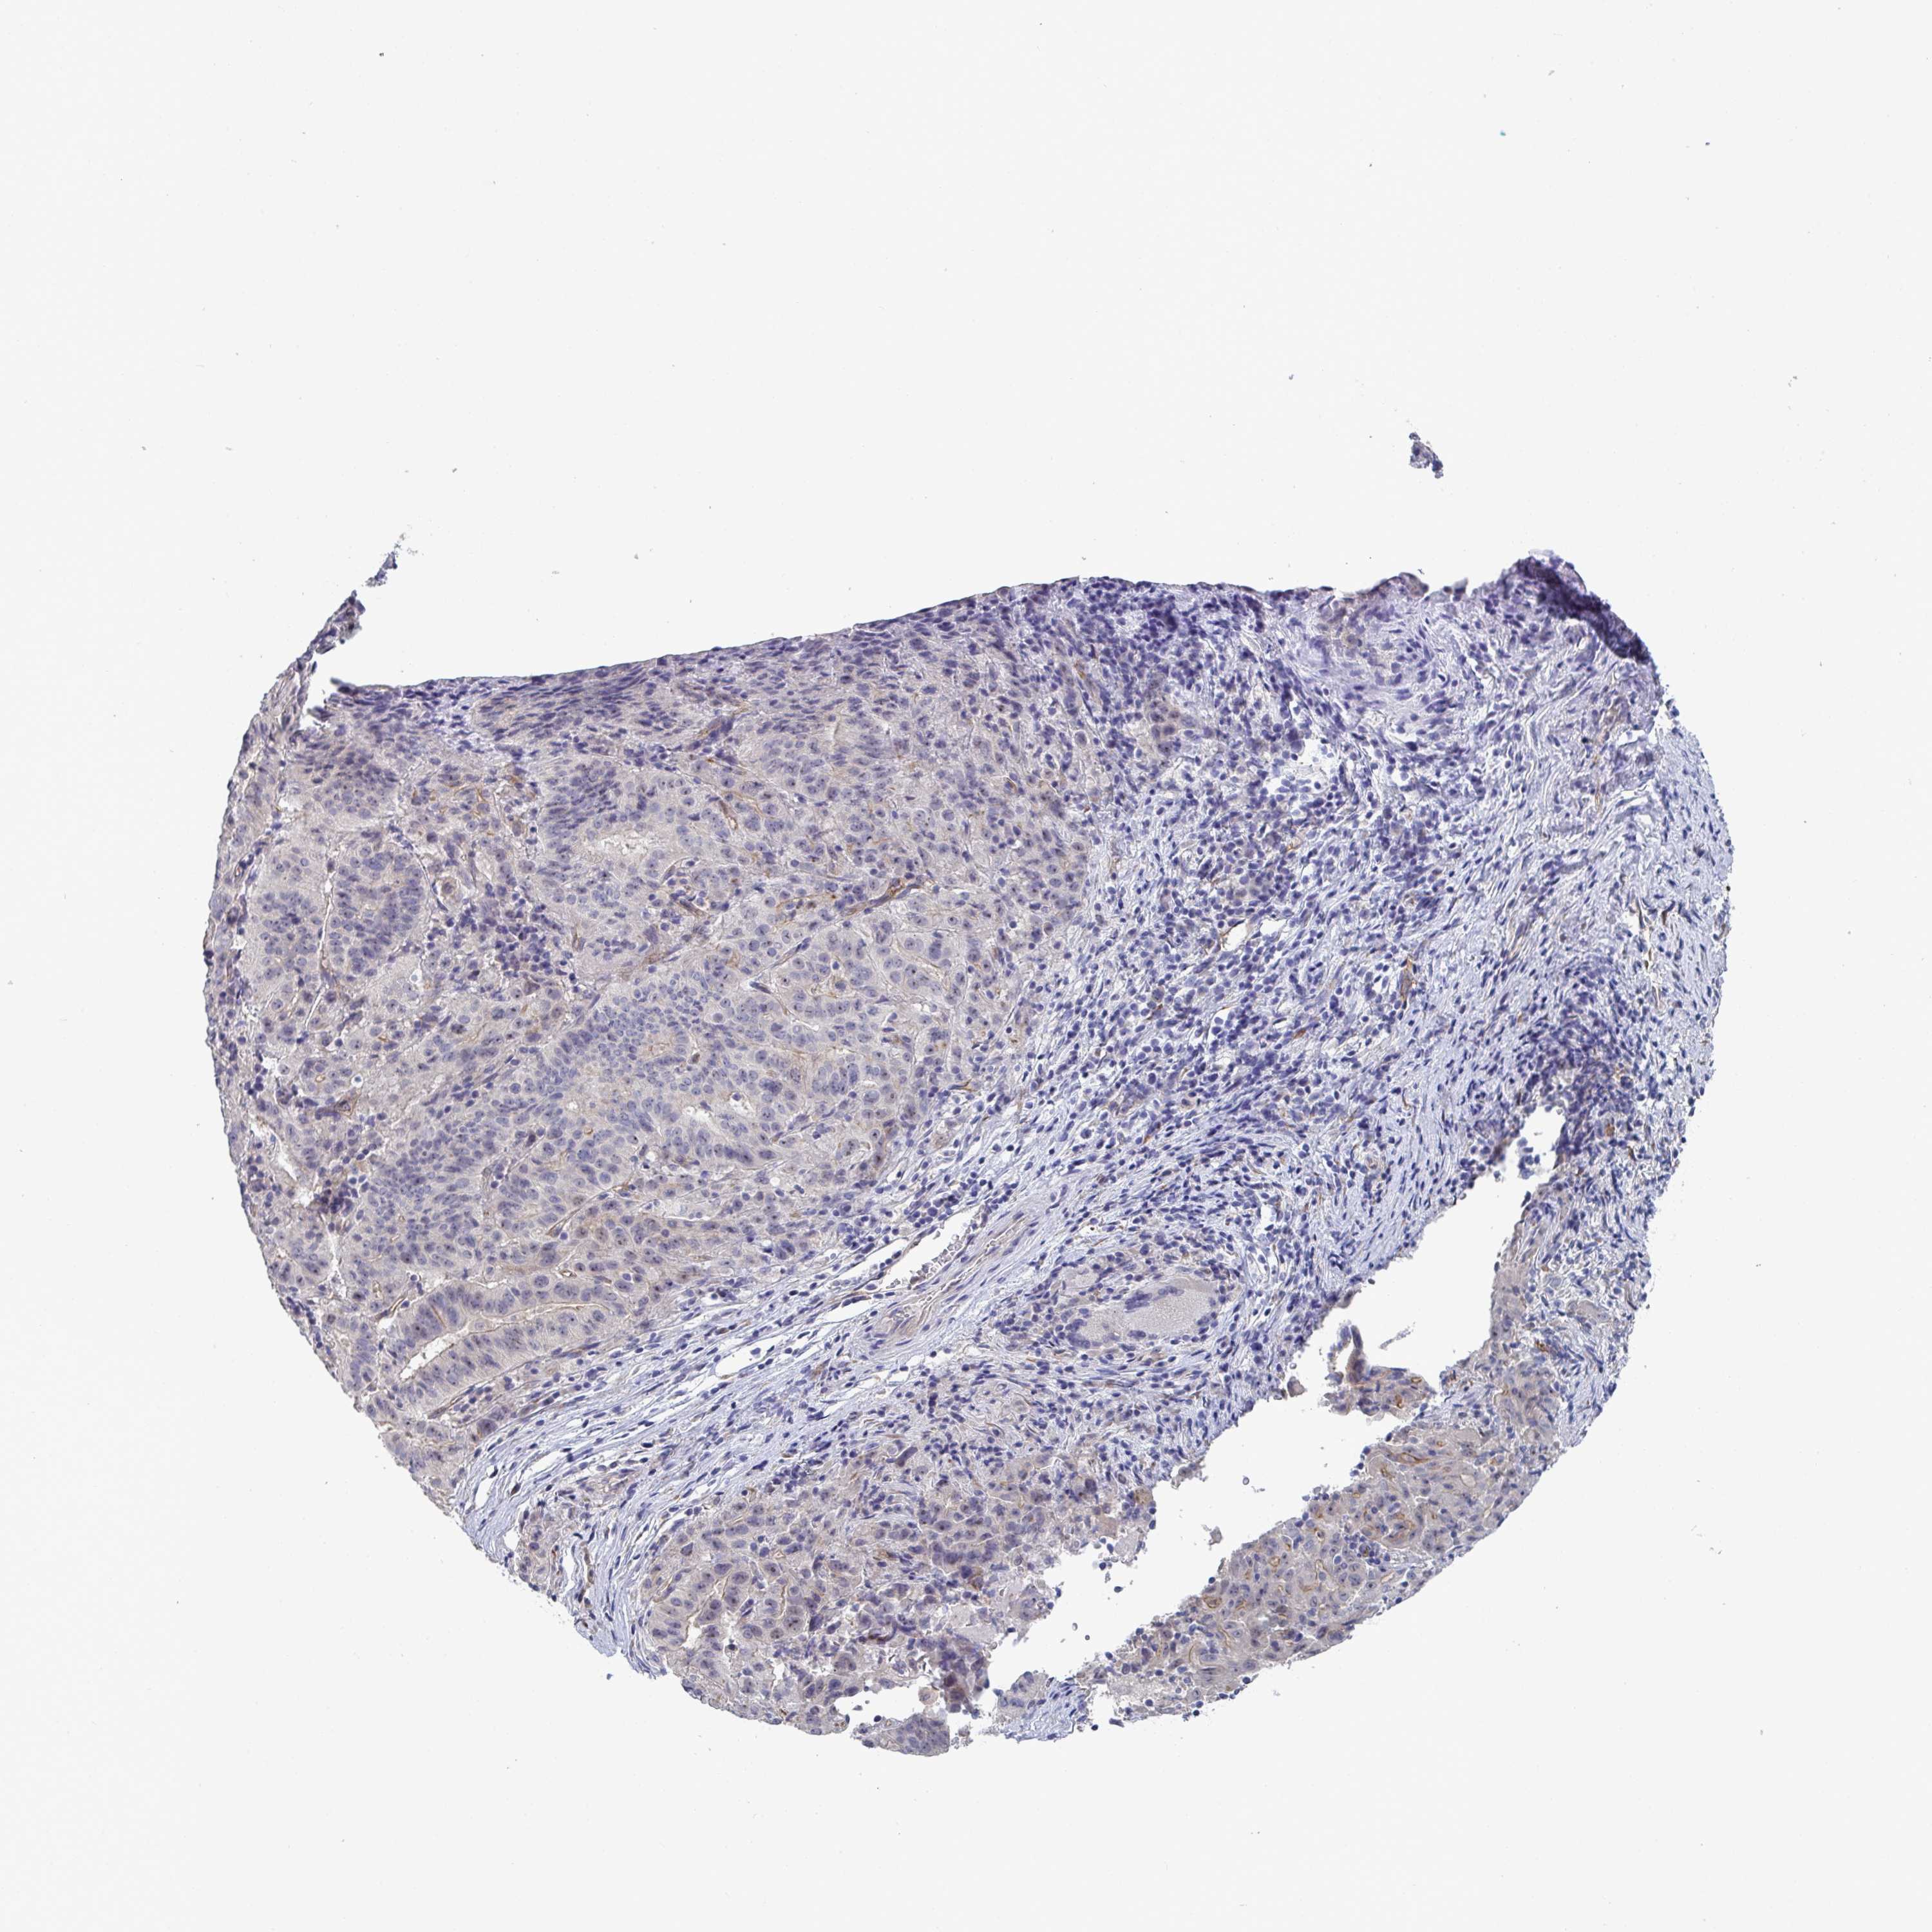

PANCREATIC CANCER - Protein expressioni

A mouse-over function shows sample information and annotation data. Click on an image to view it in a full screen mode. Samples can be filtered based on level of antibody staining by selecting one or several of the following categories: high, medium, low and not detected. The assay and annotation is described here.

Note that samples used for immunohistochemistry by the Human Protein Atlas do not correspond to samples in the TCGA dataset.

Antibody stainingi

Antibody staining in the annotated cell types in the current human tissue is reported as not detected, low, medium, or high, based on conventional immunohistochemistry profiling in selected tissues. This score is based on the combination of the staining intensity and fraction of stained cells.

Each image is clickable and will lead to virtual microscopy that enables deeper exploration of all samples and also displays staining intensity scores, fraction scores and subcellular localization as well as patient and tissue information for each sample.

Antibody HPA056258

Staining

High

Medium

Low

Not detected

Intensity

Strong

Moderate

Weak

Negative

Quantity

>75%

75%-25%

<25%

None

Location

Nuclear

Cytoplasmic/membranous

Cytoplasmic/membranous,nuclear

Adenocarcinoma, NOS